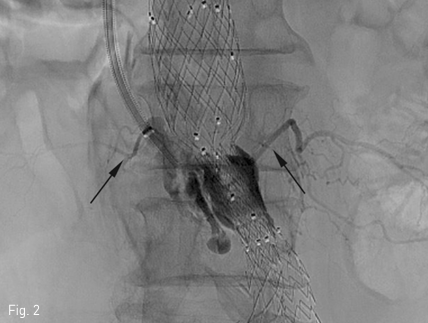

초음파 유도 하에 우측 내경정맥을 천자하여 Rosch-Uchida transjugular liver access set (Cook, Bloomington, IN, USA) 에 포함된 10F sheath 를 하대정맥에 삽입한 뒤 sheath tip 은 제3 요추의 상연에 위치시켰음. 이후 set 에 포함된 14G stiffening cannula에 Rosch-Uchida needle 을 삽입하고 투시의 전후 및 측면 영상을 이용하여 needle의 위치와 천자방향을 확인한 뒤 하대정맥에서 대동맥류를 직접 천자하였음. 이후 needle tip을 동맥류내의 제3-4 요추사이공간 level 의 제3 허리동맥 기시부로 위치시키고 혈관조영술을 시행하였음. 혈관조영술에서 type II endoleak 의 원인이 되는 제3 허리동맥이 관찰되었으며(Fig. 2), 이를 N-butyl cyanoacrylate 와 lipiodol 을 1:2 로 혼합한 용액 4.5mL 를 주입하여 색전술을 시행하였음. 시술 중 시행한 Fluoroscopy 와 시술 후시행한 CT에서 모두 표적인 제3 허리동맥 내부에 lipiodol 이 차 있는 것을 확인한 뒤 시술 종료하였음(Fig. 3)

Fig 3a

Fluoroscopy during the embolization (A) and immediate post-embolization CT (B) shows N-butyl cyanoacrylate and lipiodol mixture fills within the aneurysmal sac and lumbar arteries.